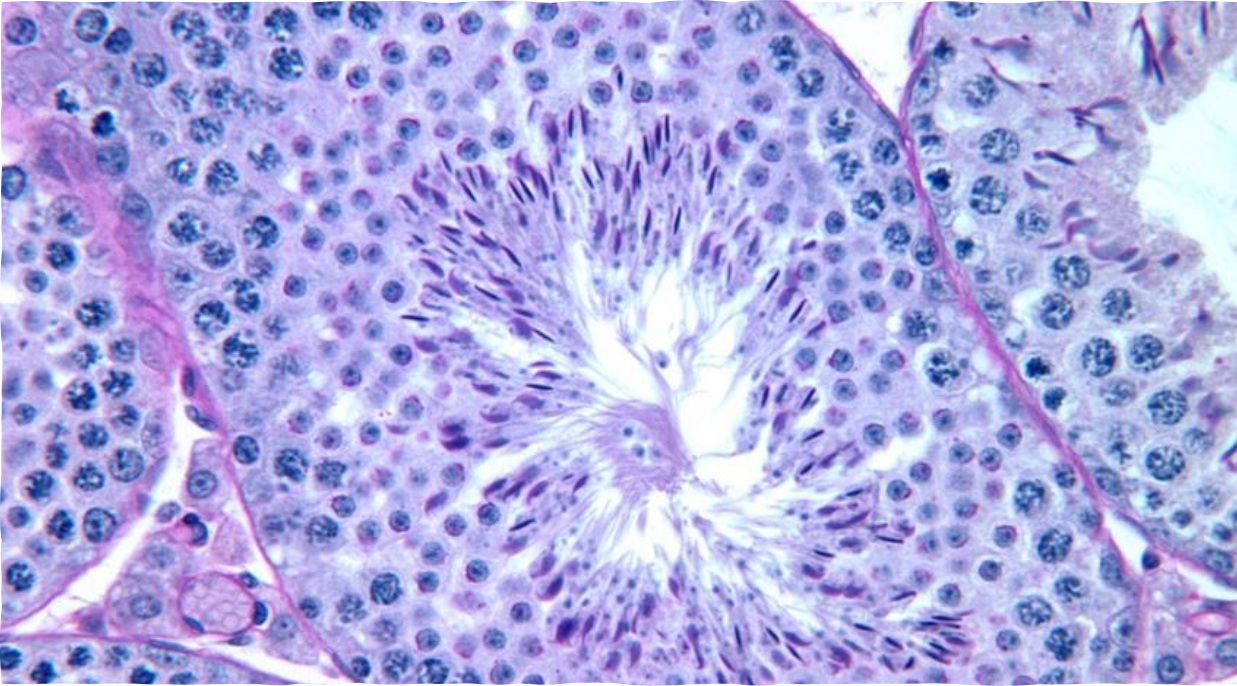

Testis